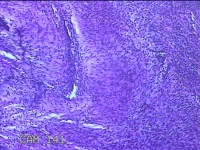

右侧卵巢囊肿

性别

女

年龄

19岁

临床诊断

一般病史

下腹痛1小时。

标本名称

大体所见

灰白暗红色囊壁样组织11x4.5x2.3cm两块,表面糜烂,因已切开,囊内容物已流失,囊壁厚0.1cm。